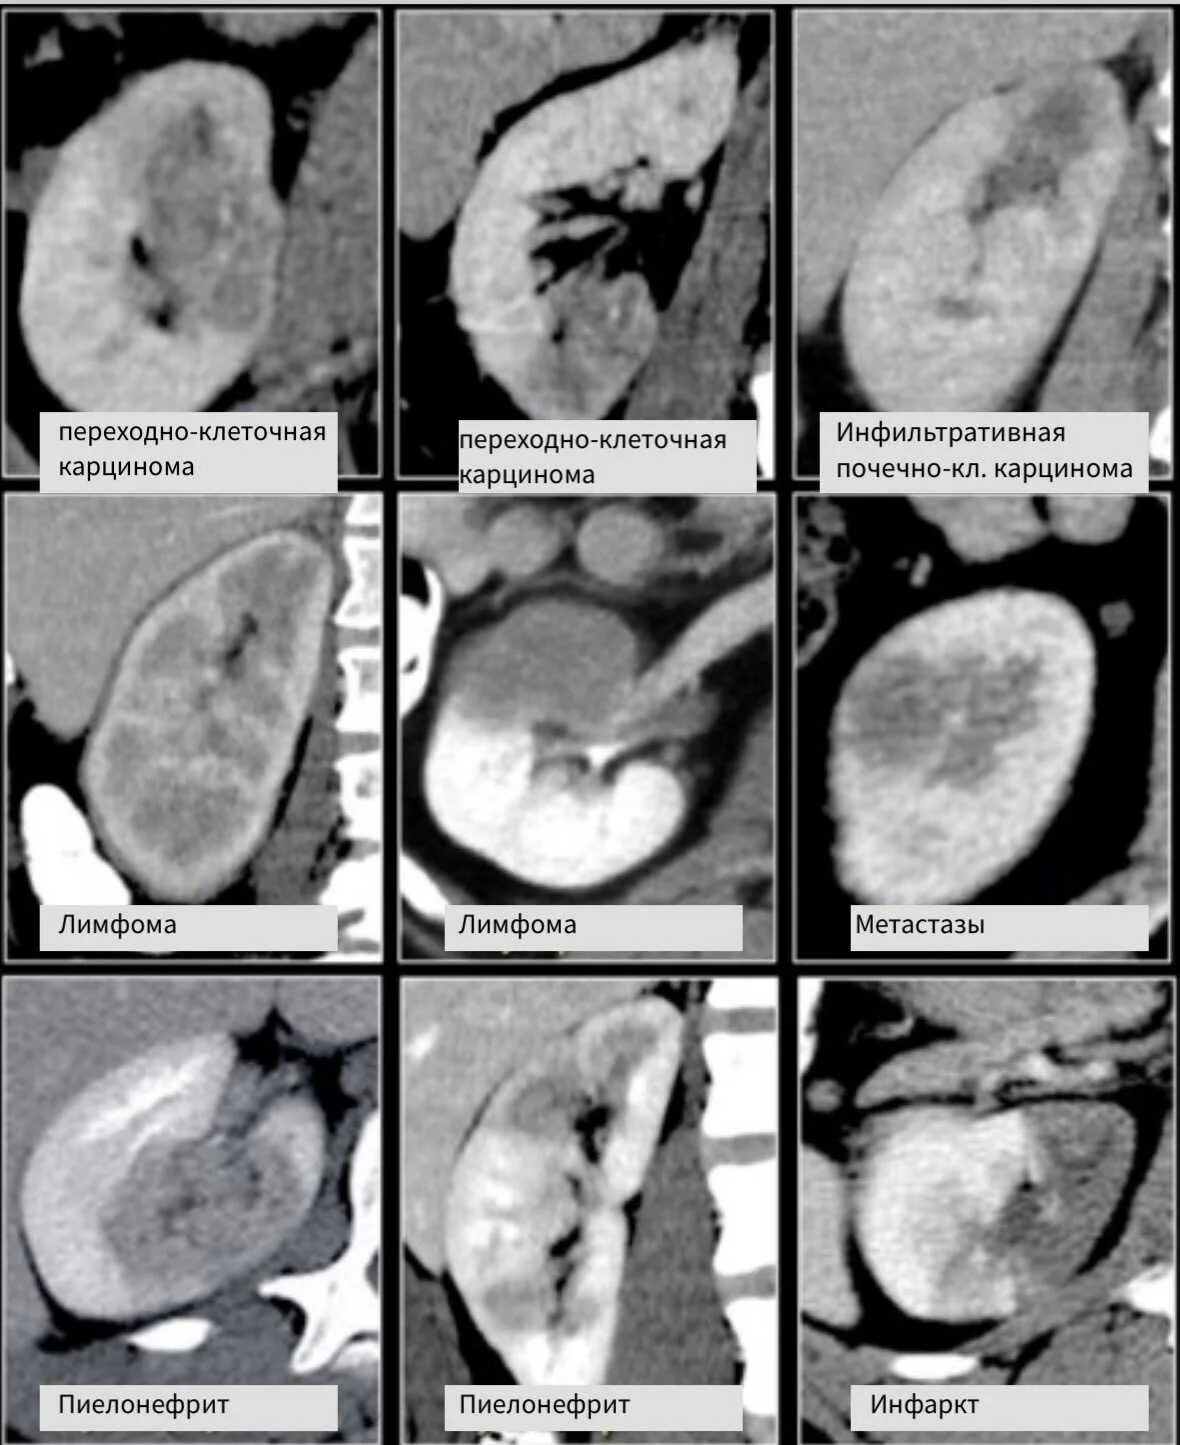

Узловых солидных образований